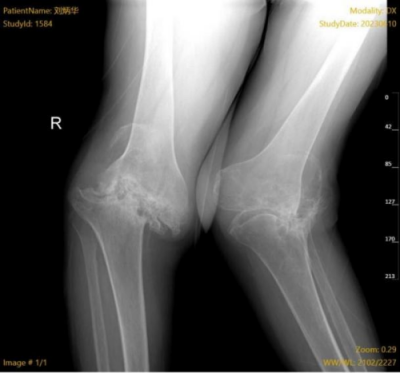

入院时患者双膝影像

入院后,骨科团队对该患者的病情进行了全面评估,发现患者的双膝重度屈曲畸形,屈伸受限,不能站立。拍片检查显示,患者的双膝关节结构关系混乱,关节重度脱位,并且关节面完全吸收,正常结构的关节骨质缺失短缩大约8cm。进一步的辅助检查还发现,患者的血沉、D二聚体严重超标,凝血功能异常。面对如此棘手的病情,骨科团队没有退缩,决定为患者实施关节置换手术,改善患者的生活质量。